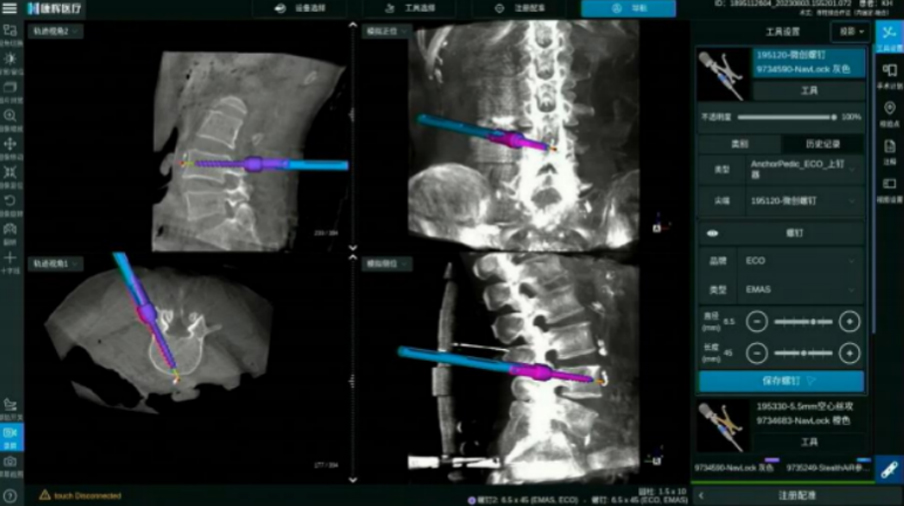

ECO/Anchor與導航化學連接 螺紋級可視

電動手柄配合導航實現可視化動力置釘

· 無導絲置釘流程, 手術更加精準安全

· 開路、絲攻、置釘,手術全程步步實時可視

· 實時呈現手術工具、 內植入物清晰邊界

· 可拓展至椎間處理步驟 三維實時可視